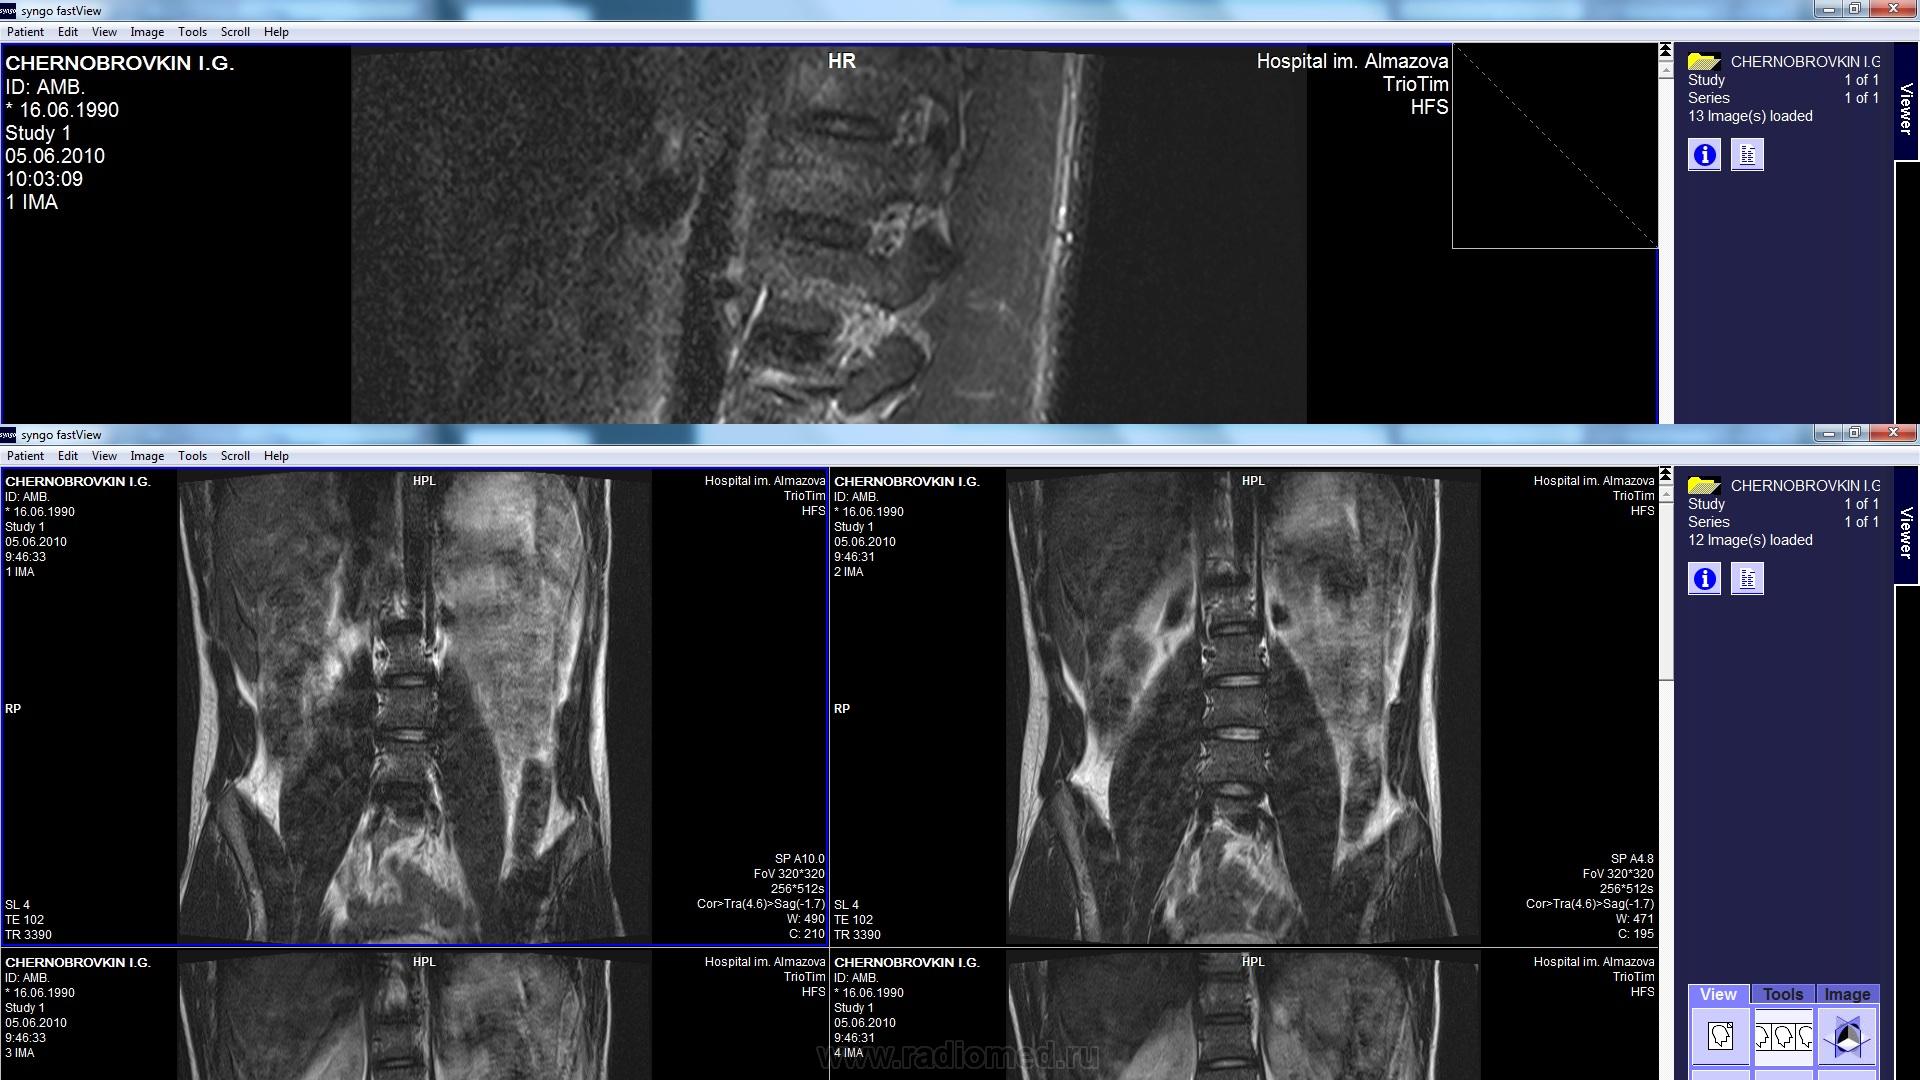

Представленные на картинках снимки диагностической ценности не представляют (бесполезны совсем). Надо содержимое диска запаковать в zip и выложить на файлообменник. Угол искривления (степень сколиоза) измеряется на рентгеновских снимках.

судя по почти неинформативным коронарным проекциям, выраженной сколиотической деформации пояснично-крестцового отдела позвоночника нет

хотелось бы увидеть все исследование